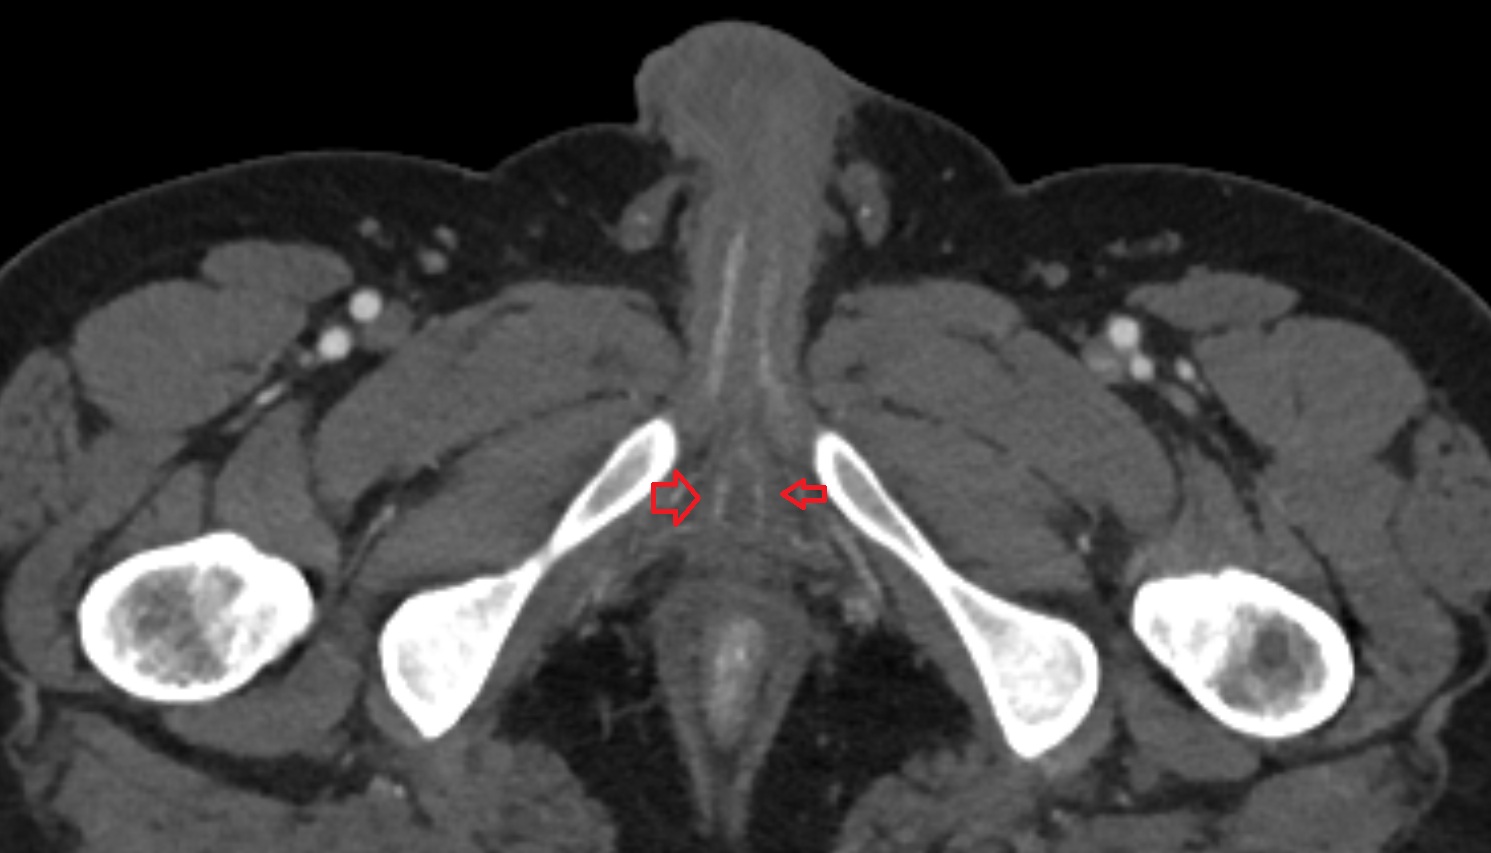

- Corpus cavernosum

- Corpus spongiosum

- Bulb of Penis

- Crus of penis